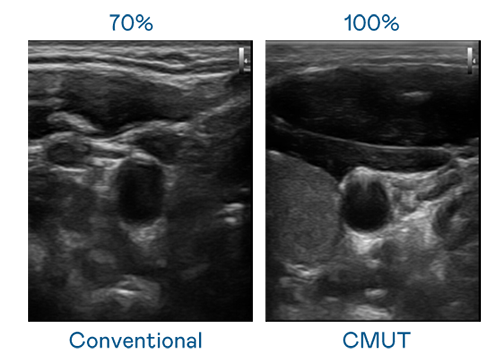

CMUT 技术是一种用电容式微机电元件来产生超音波讯号的技术。与传统 PZT 压电式技术相比,CMUT 频宽增加 30%,更宽频的超音波讯号让影像解析度大幅提升,是实现高影像品质医疗超音波扫描、促进精准医疗发展的关键技术。

超音波影像的解析度高低,首先取决于探头能发出的讯号频宽。门徒娱乐 CMUT 可提供高清晰的超音波讯号,提供高频宽、高灵敏度、影像纹理细节更高的超音波影像,协助医护人员缩短影像判读时间及利用精准的医疗影像进行诊断。